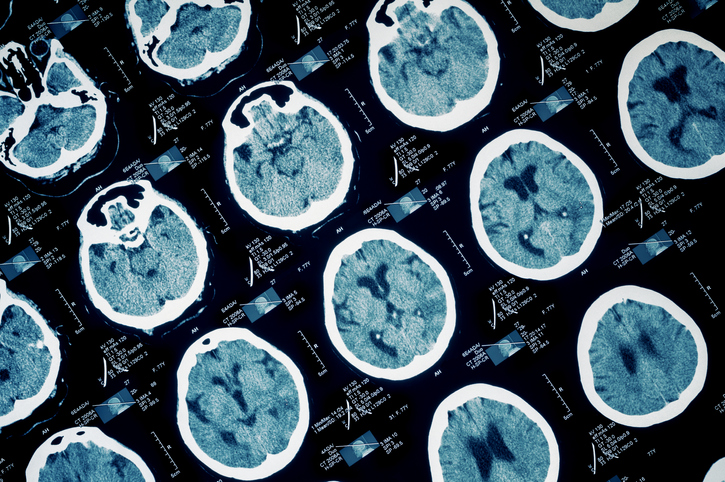

Our Sickle Cell Collaborative is focused on continuity of care, disease management and preventing gaps in care. We offer an interdisciplinary team approach that integrates multiple specialties through collaboration, ensuring that patients receive the best care throughout their lifetime.